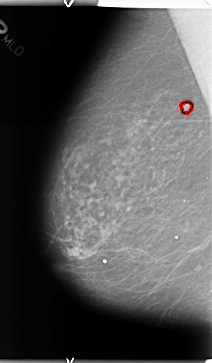

FILE: B_3126_1.LEFT_MLO.OVERLAY

TOTAL_ABNORMALITIES 1

ABNORMALITY 1

LESION_TYPE CALCIFICATION TYPE PLEOMORPHIC DISTRIBUTION CLUSTERED

ASSESSMENT 4

SUBTLETY 3

PATHOLOGY BENIGN

TOTAL_OUTLINES 1

BOUNDARY